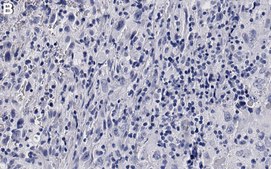

Immunohistochemistry (Paraffin) Analysis: A 1:100 dilution from a representative lot detected phospho-Rb-Ser807/811 in human lung cancer and human ovarian cancer tissue sections.